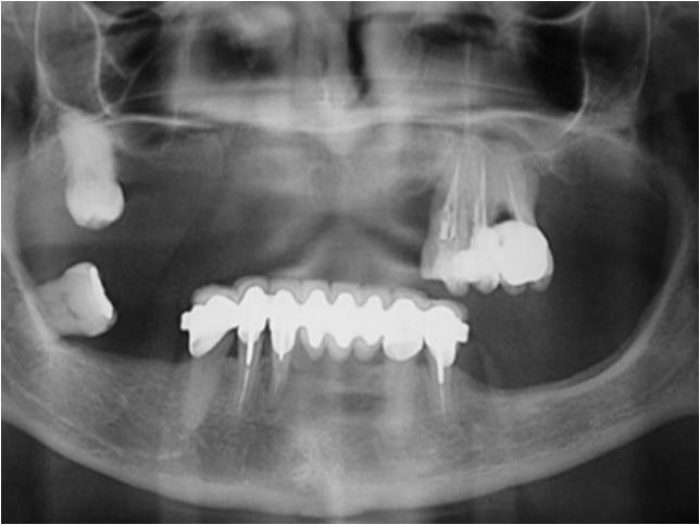

Raio X das próteses sobre implantes superiores e inferiores